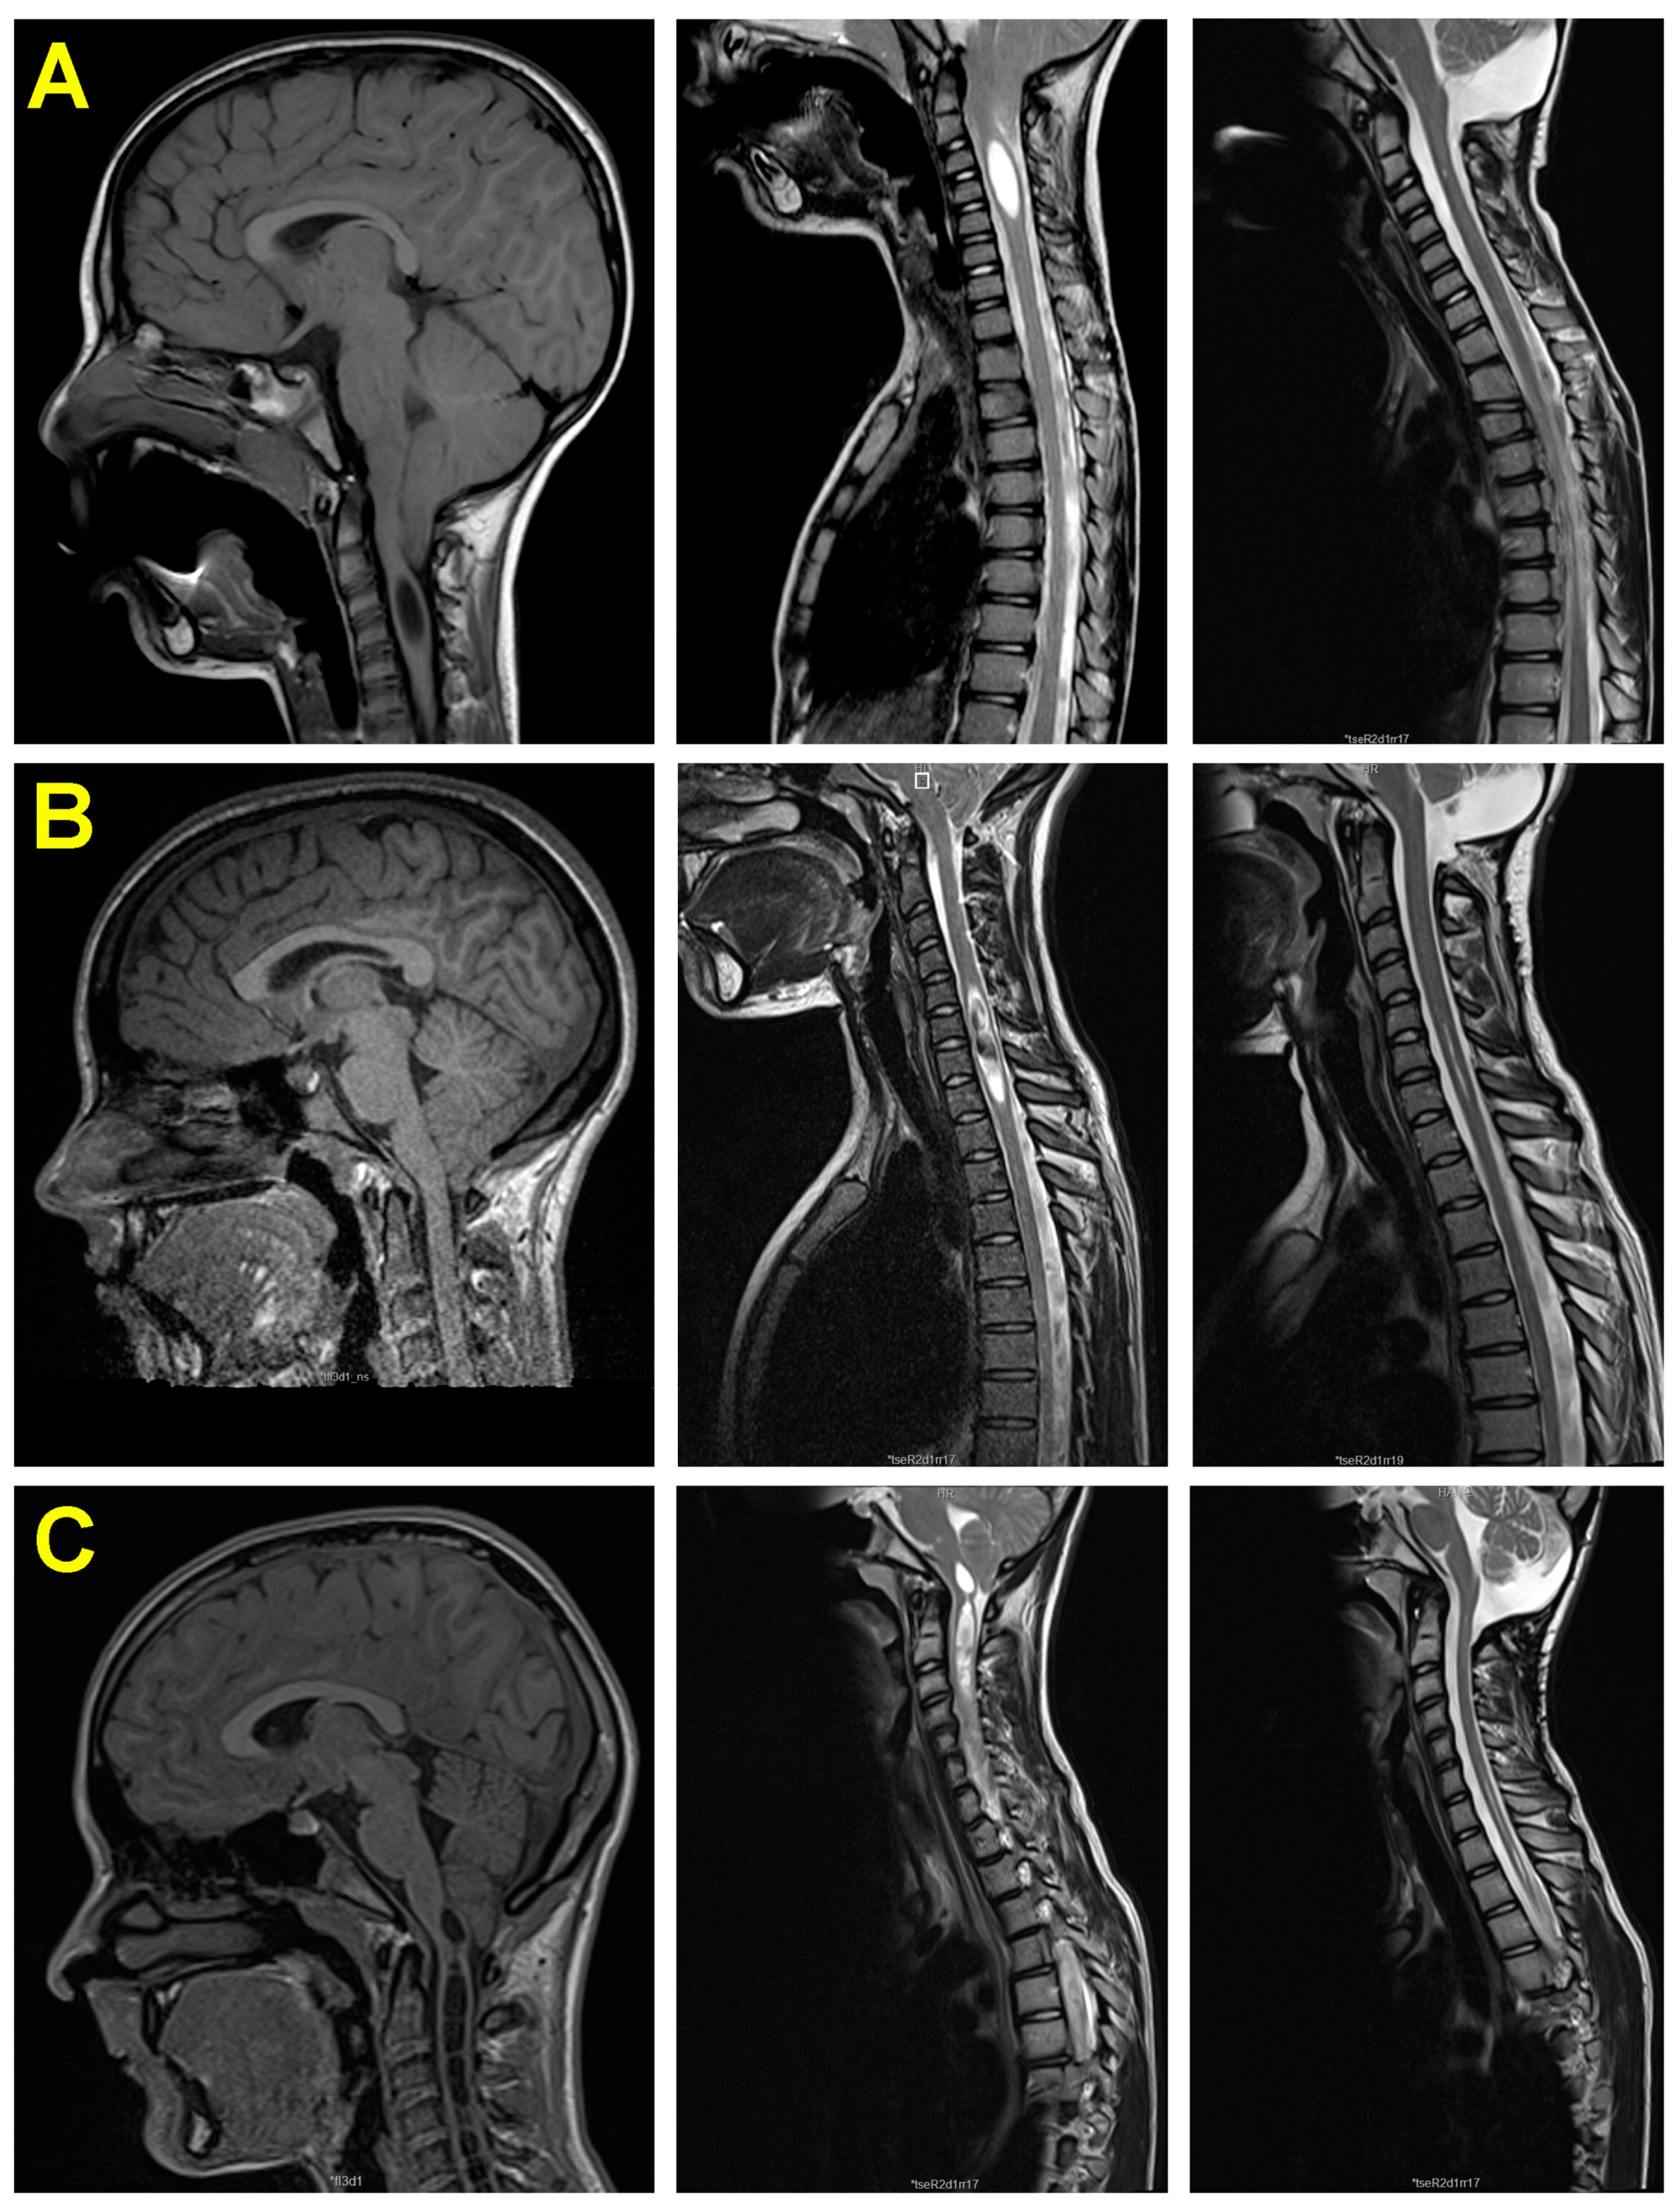

3.5. Neuroimaging Findings before and after Surgery